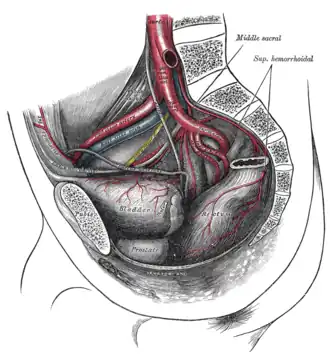

The arteries of the pelvis.

The arteries of the pelvis. -